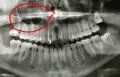

Вчера была у стоматолога, сделали снимок. Врач сказал, что пломбы на снимке хорошие, каналы запломбированы хорошо, ровно. Но, видит на кончике корня маленькое как будто воспаление. Сказал, что это может быть из-за простуды. Лечить не нужно, дал направление в физ.кабинет.